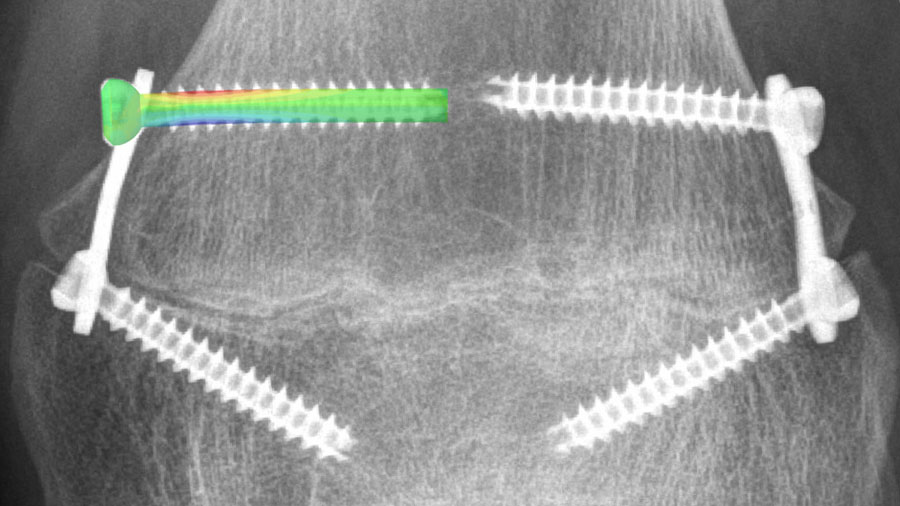

The Biomedical Development program offers extensive know-how, expertise, and experience in the fields of biomechanical testing and computational analyses to advance patient care.